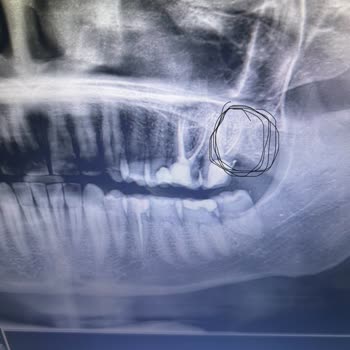

Kendi paramla rezil olmak bir yana, sağlığımdan olmak ayrı bir sorumsuzluk. 20 diş çektirdim, kemik kaldı ama 'size sıkıntı yapmaz' dediler. Sorun yok diyerek göz ardı ettim. Yanımdaki dişe kanal tedavisi yapılacaktı. Diş hekimi, kanalın içinde iğne kırdı ve çıkarılmasının mümkün olmadığını söyledi....